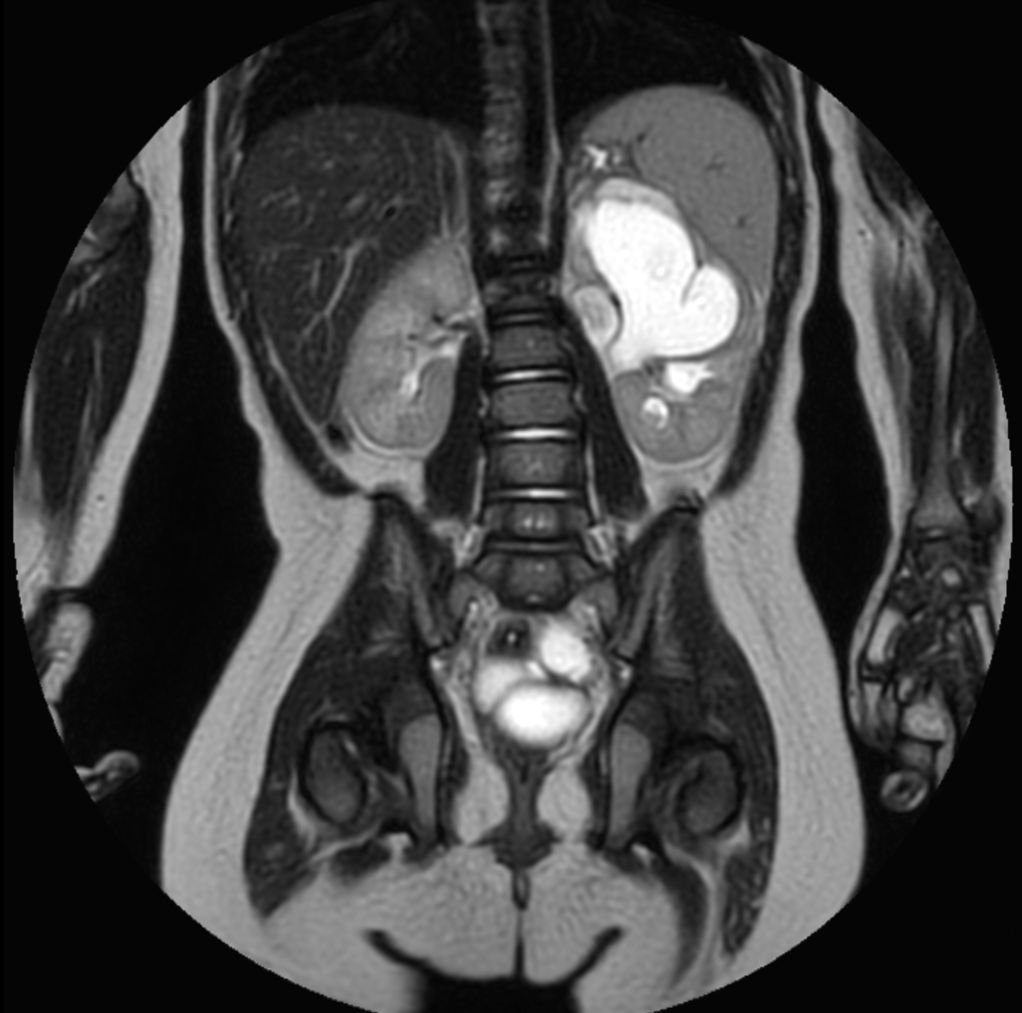

Coronal T2w MultiVane XD